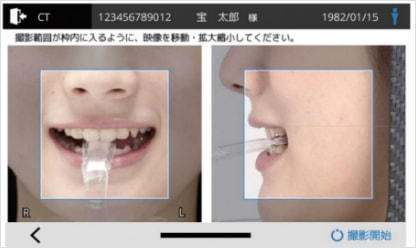

タッチパネル画面の映像を見ながら、容易に位置付けできる2方向カメラスカウト

タッチパネルでの画面操作と連動して、撮影装置が位置を合わせるので、患者さんは動く必要がありません。

またカメラスカウトに加え、2方向のレントゲンスカウト撮影で、撮影位置を設定することもできます。

位置付け時、患者さんの正面と側面に備え付けられたカメラで、2方向からの顔貌撮影を行います。

その画像はタッチパネル画面に表示され、ダイレクトな操作で撮影位置や撮影範囲の設定を行うことができます。

さらに、位置決め時のスカウト撮影画像は撮影画像と共に記録されます。

CTやパノラマ撮影に関わるスタッフの初期教育への活用や、撮影時位置付けの再現性向上にも役立てることができます。